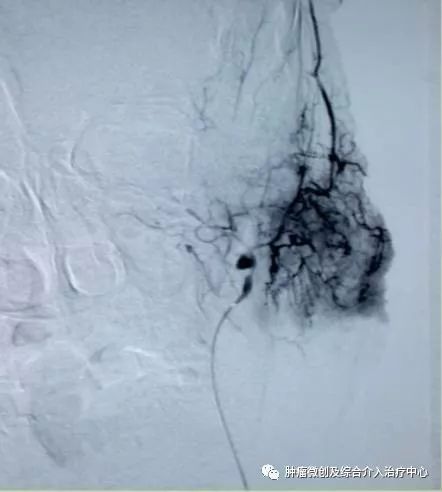

(介入栓塞病变血管后,DSA示肿瘤病变血管栓塞好,血管走向清晰,出血停止)项目介绍:头颈部良、恶性肿瘤临床常见,其良性见于鼻咽纤维血管瘤,恶性者见于鼻咽、鼻窦癌,颈部转移性肿瘤等; 传统止血治疗疗效有限,给患者及家属带来极大的精神压力,介入手术栓塞病变血管可达到确切的止血效果,并致病变缺血萎缩。04急性肺栓塞介入手术治疗